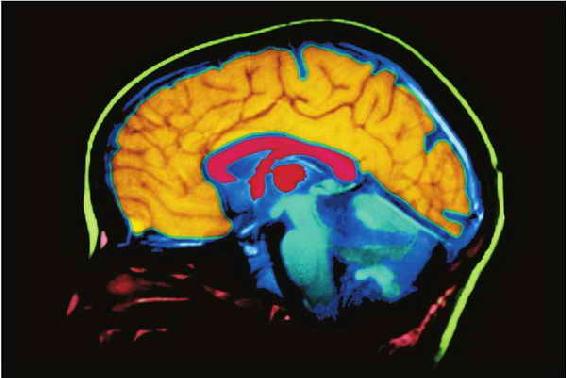

脑成像技术能够使研究者比过去更多地了解大脑对行为和人格所起到的作用。